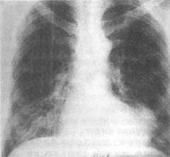

1、疑有分流性先天性心臟病。2、獲得性心臟病的診斷:心瓣膜病、心包積液、心肌病、大血管瘤、心房粘液瘤、室壁瘤、上腔靜脈梗阻等。3、心臟病術後的隨訪及療效的觀察。4、碘過敏或病情嚴重不能接受X線心血管造影者。

對先天性心臟病及心內分流的診斷,由於X線及B超的進展,此法現已較少套用。